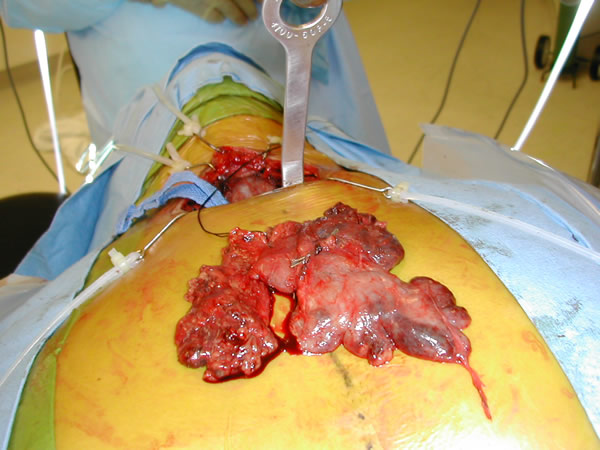

| Figure 6: Complete thymus removed. |

The gland is grasped in the midline at the level of the innominate vein and retracted anteriorly and to the left and the posterior aspect of the gland dissected sharply to the AP window. Once this is complete the left upper margin of the gland is dissected anteriorly from the phrenic nerve in the region of the AP window. With this the gland is freed from the mediastinum and is removed through the cervical incision (Video 11, Figure 6). Any remaining anterior mediastinal and pericardial fat is removed (Video 12). At the conclusion of the operation the entire anterior mediastinum should be clear of thymic tissue and fat (Video 13). A medium sized Blake or JP drain is placed and the lung is re-inflated (Video 14).